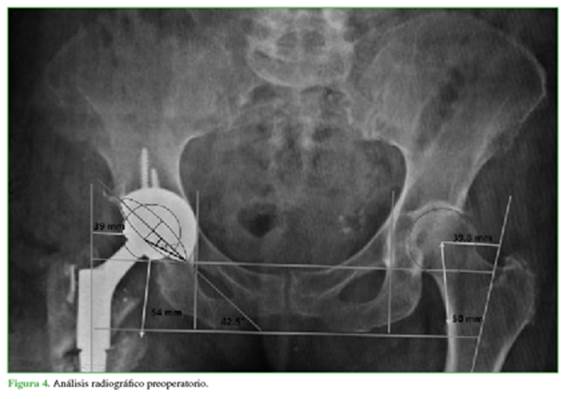

Con la primera revisión, se logró reproducir el offset de la cadera contralateral y se evidenció una discrepancia de longitud de 4 mm a predominio de la cadera operada. En cuanto a la copa acetabular, se encontró con una inclinación de 42,5° y una anteversión de 16,7°, evidenciadas por el método de Liaw.12 Además, no se visualizaron signos de aflojamiento en ninguno de los componentes (Figura 4). Se descartó columna rígida mediante radiografías de columna lumbosacra con la paciente de pie y sentada, midiendo la inclinación sacra.